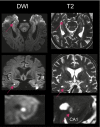

Autobiographical memories in our lives are critically dependent on temporal lobe structures. However, the contribution of CA1 neurons in the human hippocampus to the retrieval of episodic autobiographical memory remains elusive. In patients with a rare acute transient global amnesia, highly focal lesions confined to the CA1 field of the hippocampus can be detected on MRI. We studied the effect of these lesions on autobiographical memory using a detailed autobiographical interview including the remember/know procedure. In 14 of 16 patients, focal lesions in the CA1 sector of the hippocampal cornu ammonis were detected. Autobiographical memory was significantly affected over all time periods, including memory for remote periods. Impairment of episodic memory and autonoetic consciousness exhibited a strong temporal gradient extending 30 to 40 y into the past. These results highlight the distinct and critical role of human hippocampal CA1 neurons in autobiographical memory retrieval and for re-experiencing detailed episodic memories.